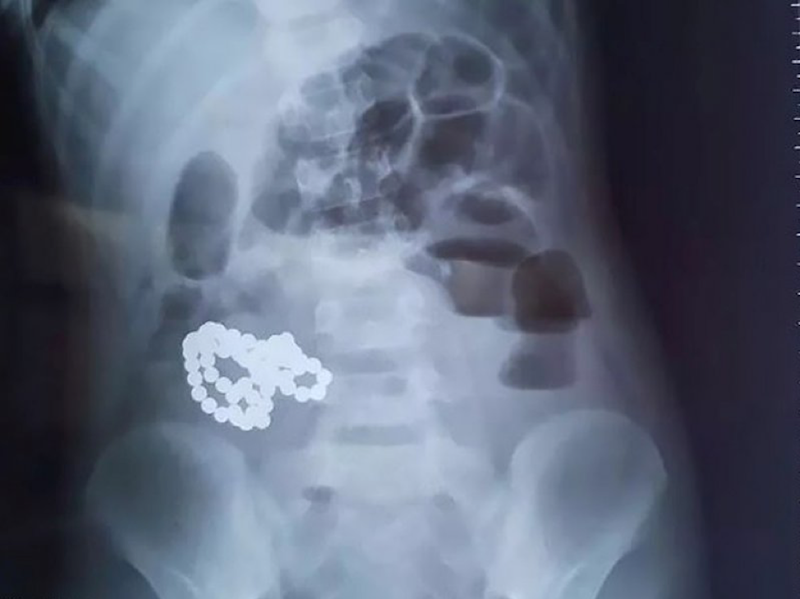

Основной инструментальный метод диагностики — рентгенография брюшной полости. Пациент должен стоять, в случае тяжелого состояния — лежать на боку. В первые часы болезни на рентгенограмме видны раздутые, поперечно исчерченные петли кишечника. Позже становится заметен классический признак непроходимости кишечника — чаши клойбера. В петлях кишечника видны уровни жидкости с воздухом над ними.

Если кишечная непроходимость вызвана инородным телом, рентгенограмма это покажет.